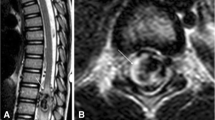

Spinal and cerebral vascular malformations are manifestations of underlying vascular dysplasia [12]. These lesions represent abnormal arteriovenous connections that failed to differentiate properly into arteriolar, capillary, and venular channels [13]. On magnetic resonance imaging (MRI), CVMs appear as areas of serpiginous flow voids insinuating into the brain parenchyma (Fig. 11). Patients with HHT often have multiple malformations of various types, some of them with an atypical or indeterminate MRI appearance [14]. Cerebral angiography may be required for diagnosis of equivocal lesions and for planning of treatment. The therapy for symptomatic CVMs is surgical resection, stereotactic radiosurgery, embolization, or a combination of these treatments [15].

Rodesch G, Hurth M, Alvarez H, Tadie M, Lasjaunias P (2002) Classification of spinal cord arteriovenous shunts: proposal for a reappraisal—the Bicetre experience with 155 consecutive patients treated between 1981 and 1999. Neurosurgery 51:374–379; discussion 379–380